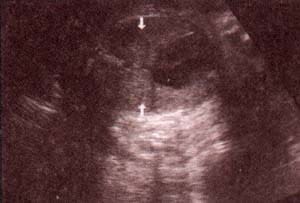

| fig 30. -(a). septum i-v. septum i-v. 32 semana | fig. 30.– (b). septum i-v íntegro entre las flechas. 35 semanas |